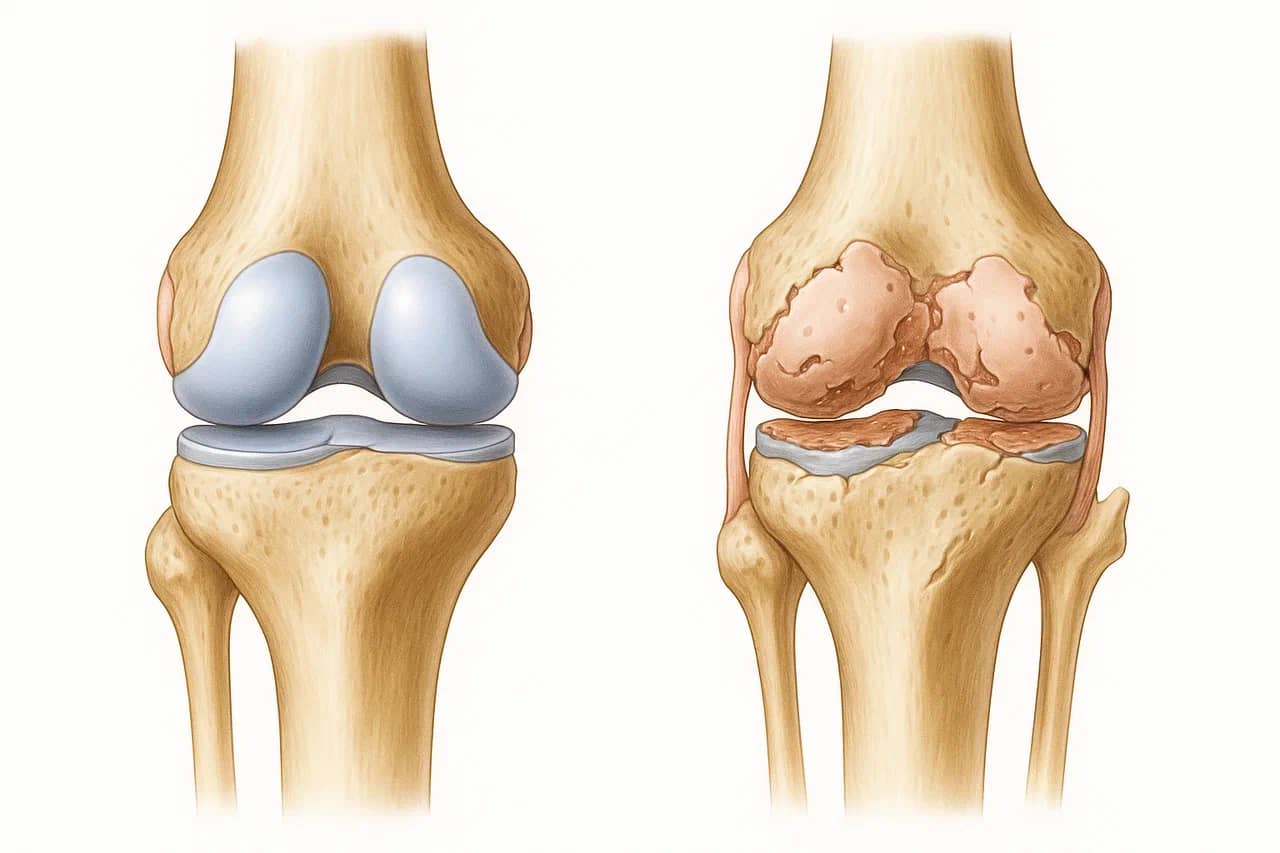

БОЛЕЗНИ И ПРОБЛЕМЫ МОЧЕПОЛОВОЙ СИСТЕМЫ, КОТОРЫЕ МОЖНО ДИАГНОСТИРОВАТЬ НА РАННЕЙ СТАДИИ